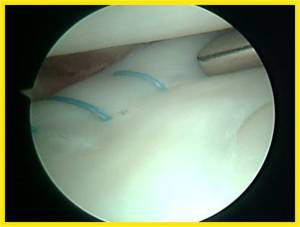

Inside-out repair of the torn meniscus.

A re-look arthroscopy in 3 months’ time showing healed meniscus.